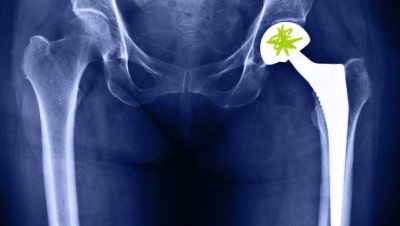

- 관리: 조기 발견이 중요, 초기에는 약물·물리치료, 진행 시 인공관절 치환술 필요

- 관리: 체중 관리, 규칙적인 운동, 약물·물리치료, 심한 경우 인공관절 수술

X-ray나 MRI로 원인을 확인하고, 물리치료·약물·주사치료 등 보존적 요법부터 시작한다.

심한 경우에는 인공관절 치환술 같은 수술적 치료가 필요하다.